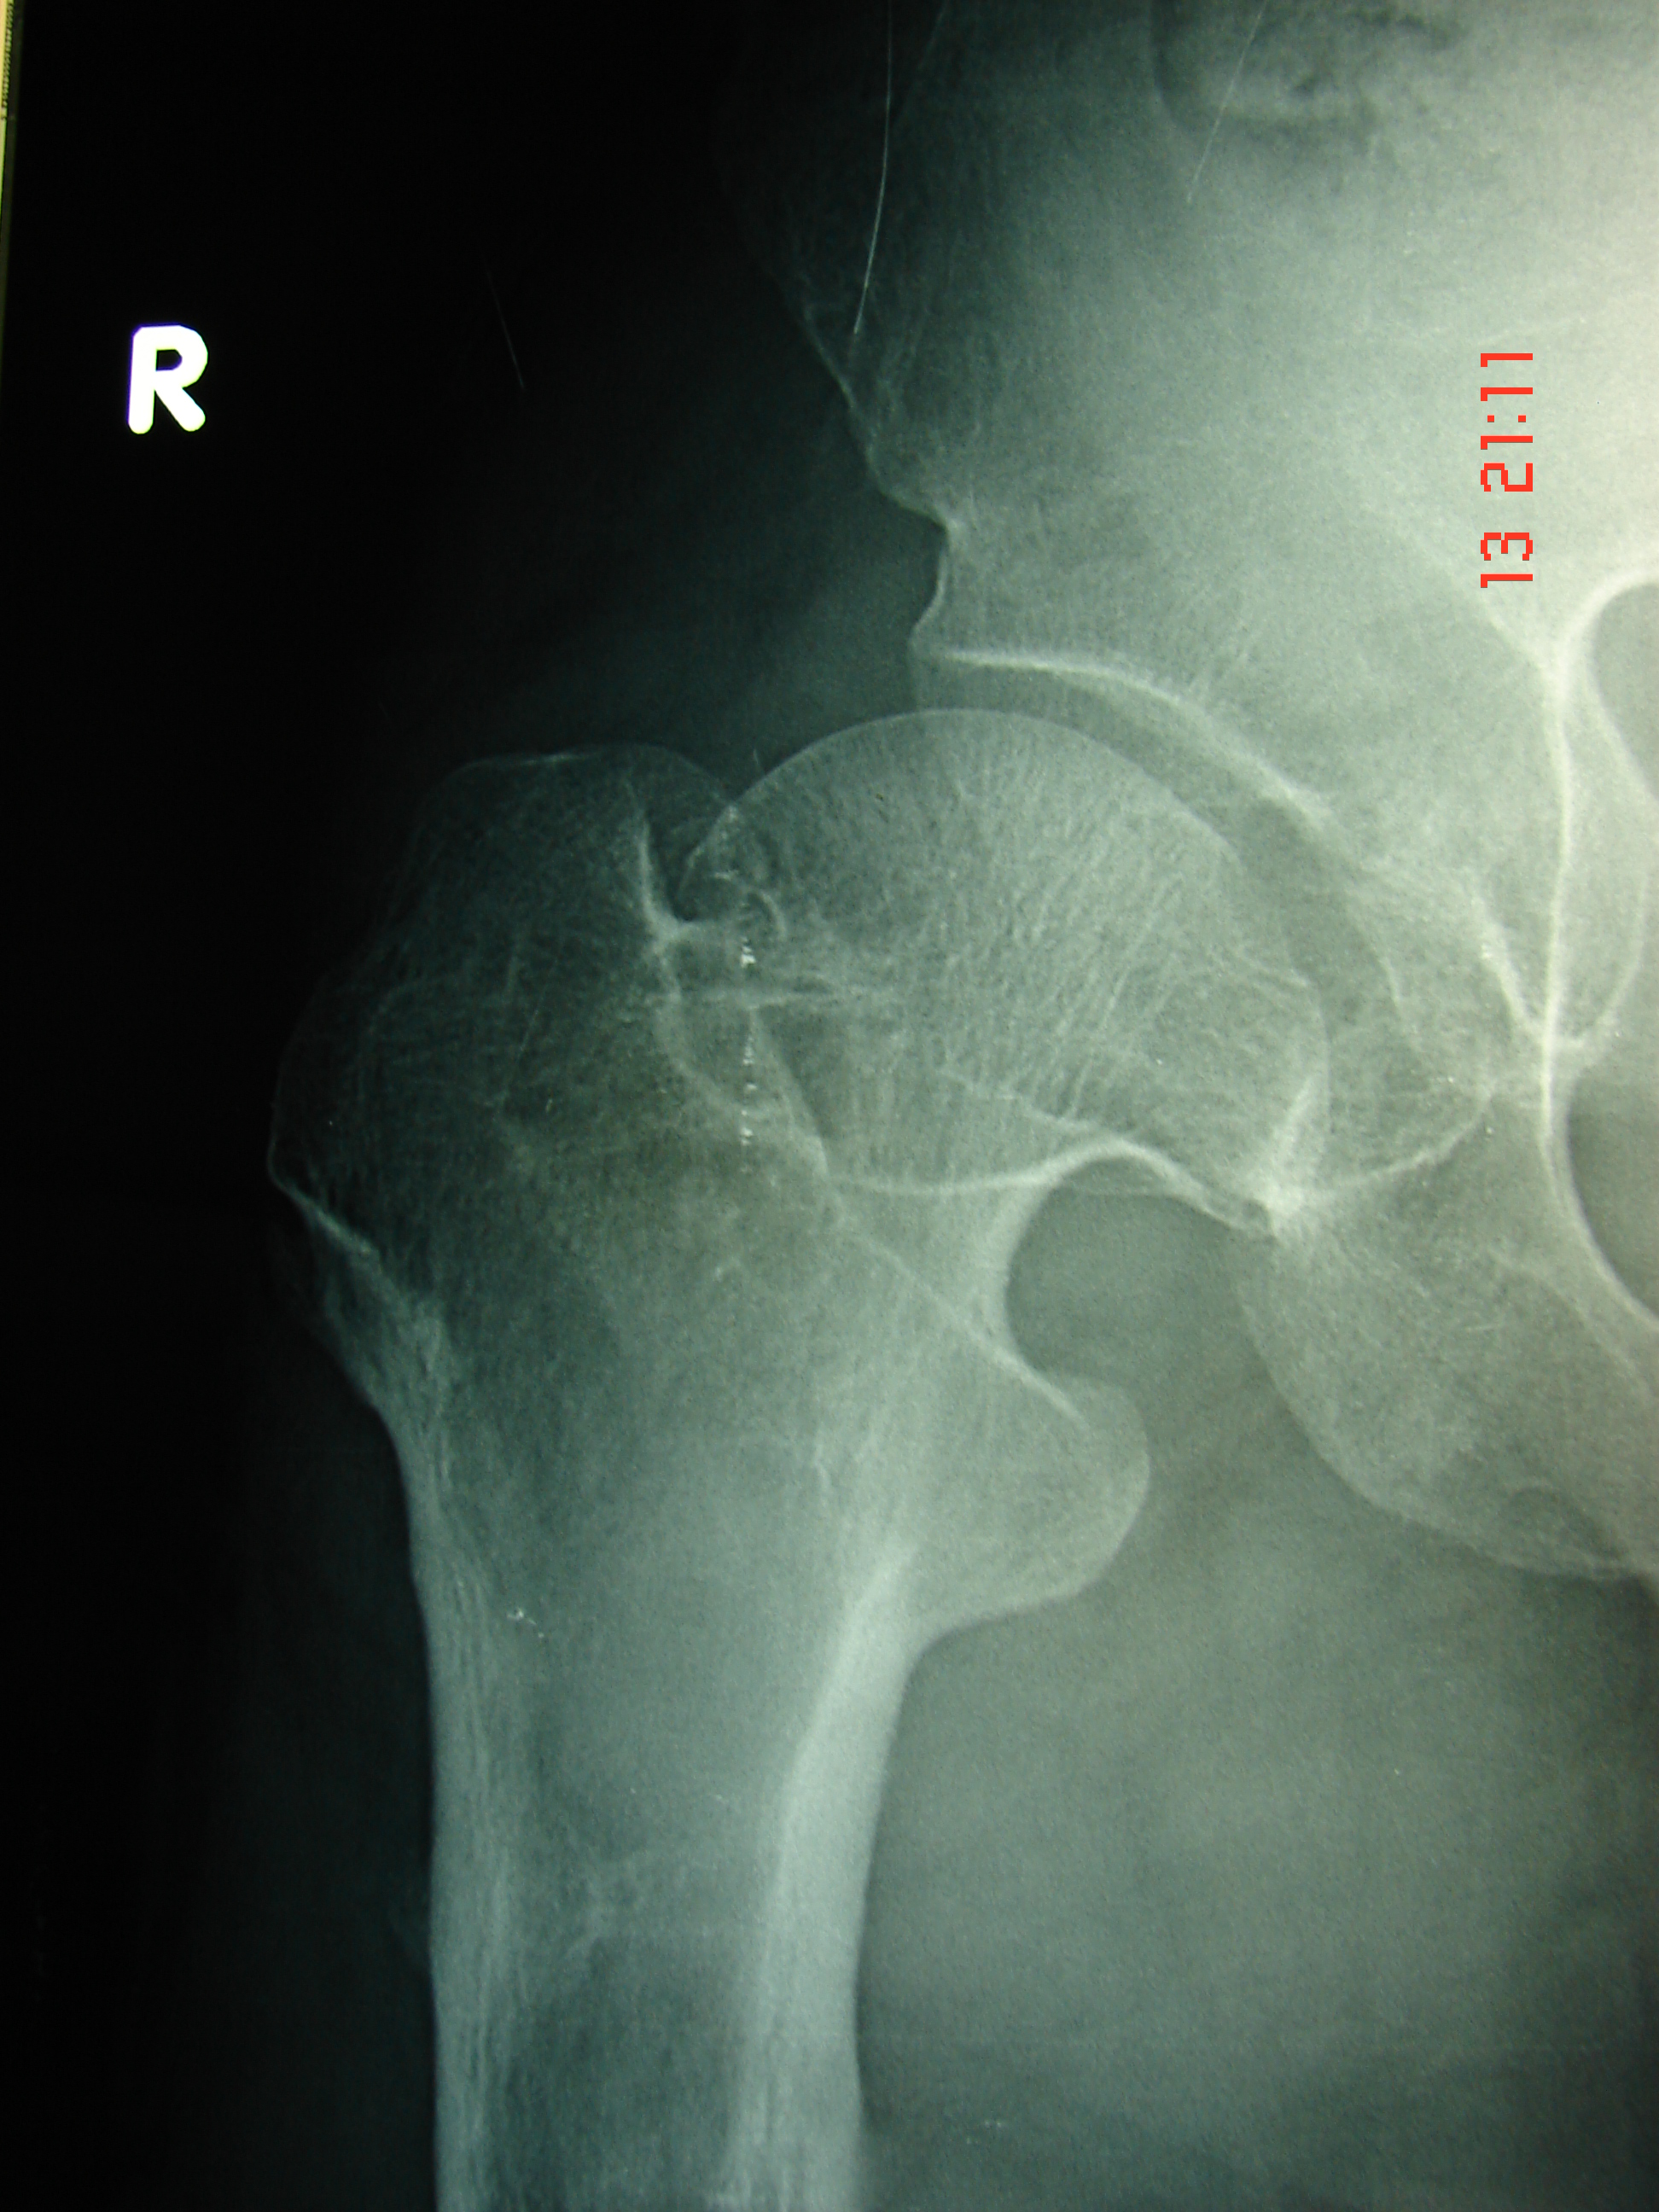

Ακτινογραφία αρθρώσεων και οστών του ΒΑ.ΠΙ., οι παρατηρούμενες παραμορφώσεις των οστών και αρθρώσεων, είναι συνήθως στα άτομα με ΑΧΟΝΔΡΟΠΛΑΣΙΑ.

Εικόνα 2: ε, ζ Μετωπιαίες ακτινογραφίες της δεξιάς και αριστερής κατ’ ισχίου άρθρωσης. Παρατηρούνται οι παραμορφώσει των κεφαλών του άνω τριτημορίου τών μηριαίων οστών καθώς και των αντίστοιχων κοτυλών, οι οποίες είναι δυσπλαστικές.